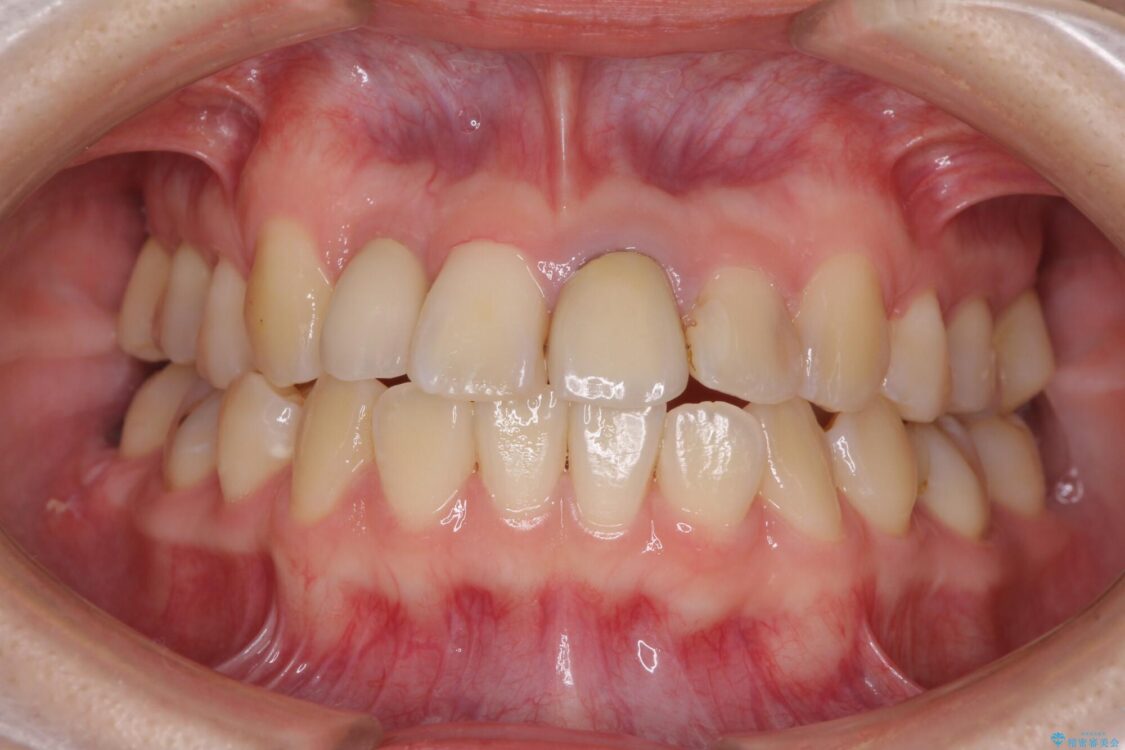

治療前

• 虫歯治療ついでに歯並びの後戻りを改善 インビザラインによる矯正治療 治療前画像

奥歯が痛いとのことで来院された患者様です。

治療計画

上顎親知らず周辺の炎症と、神経組織の失活した歯の炎症による痛みが認められたため、親知らずの抜歯と根管治療を行いました。

根管治療を行った歯はクラウンによる補綴治療が必要となりますが、高校生の頃に行った矯正治療の後戻りも気になるとのことで、補綴治療を行う前に矯正治療を行うこととしました。

後戻りは軽度であり、インビザラインにて歯列を整え、その後にオールセラミッククラウンにて補綴治療を行うこととしました。